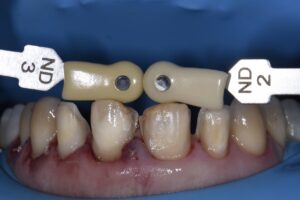

Following initial preparation from teeth 9-12 (2.1-2.4), the margins were located equigingivally.  From this point, the DSD was used as a guide to the change in cervical profile which was accomplished initially using the Ultradent Gemini diode Superpulsed laser at 1.2W in dual-wavelength mode.  The margins were relocated to this level, and a transsulcular approach using a Kois Wedelstaedt chisel was attempted and was generally successful except for a few problematic areas where re-establishment of ideal crestal distance from the margins was dubious.  A full thickness envelope flap was raised and the offending areas directly osteoplastied using the Kois Surgical System (Brasseler) prior to debriding the area and gaining primary closure using vertical mattress sutures.

The contralateral side was prepared and a traditional final impression taken using an A-silicone dual stage technique.  A digital intraoral scan was considered, however due to the tissue quality and risk of losing precious hemostasis was not used.  The provisionals are a shrink to fit situation with GC TempSmart B1 with the goal of ensuring our endpoints of gaining gingival marginal symmetry and occlusal cant leveling are achieved.